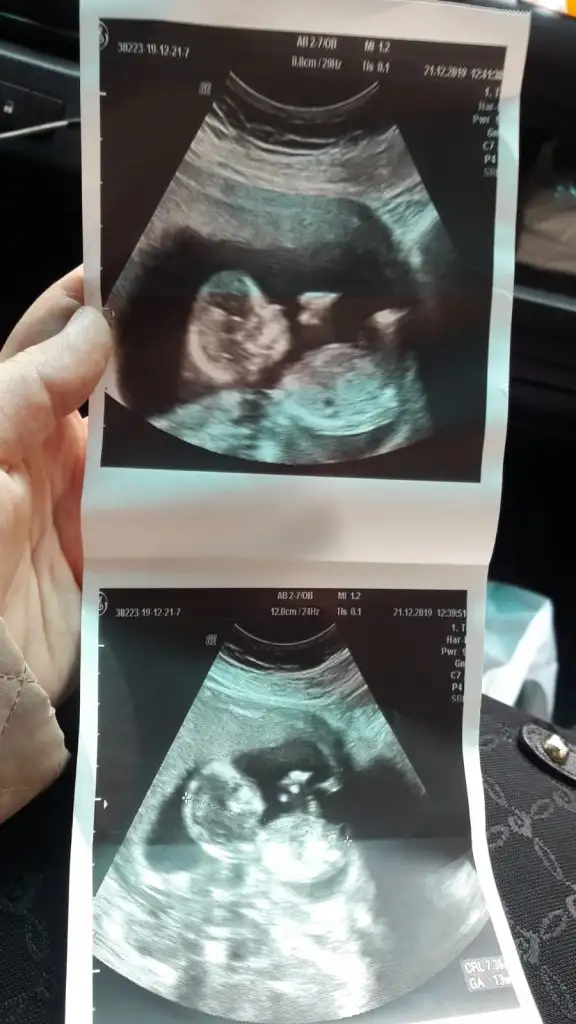

Erkek benim buyuk oglanindi. 4 hafta 10 hafta 14 haftalikKaç haftalık burada sagda ve kız buna göre

14 haftamı göremedim sadece keseye baktım. Geriside hiç birsey göremedimErkek benim buyuk oglanindi. 4 hafta 10 hafta 14 haftalik

4+6 olan usg var gerisi hiç belli degil onlarda küçük usg dedimErkek benim buyuk oglanindi. 4 hafta 10 hafta 14 haftalik

Erkek ve kız için 11 yada 12 hafta usg görüntüsü olmalı açıklamalar asagıda yazıyorrabbim herkesin gönlüne göre nasip etsin inşallah .. ecmain

[/B]Eki Görüntüle 473828 gordugunuz gibi ust taraftaki simgedende anlasildigi gibi eger cikinti paralel ise kiz

yok 30°lik bir aciyla yukari dogru bakiyorsa %99 oglunuz olacak demektir simdi bi kac ornek resimler daha koyacagim kiziminkide dahil

Eki Görüntüle 473829 bu bir erkek bebek genital nub cikintisi gayet yukarda

Eki Görüntüle 473831 simdi burada cikintilara bakin eger bel popo cizgisine paralel ise kiz

yok 30 derecelik bir aciyla yukari bakiyorsa erkek